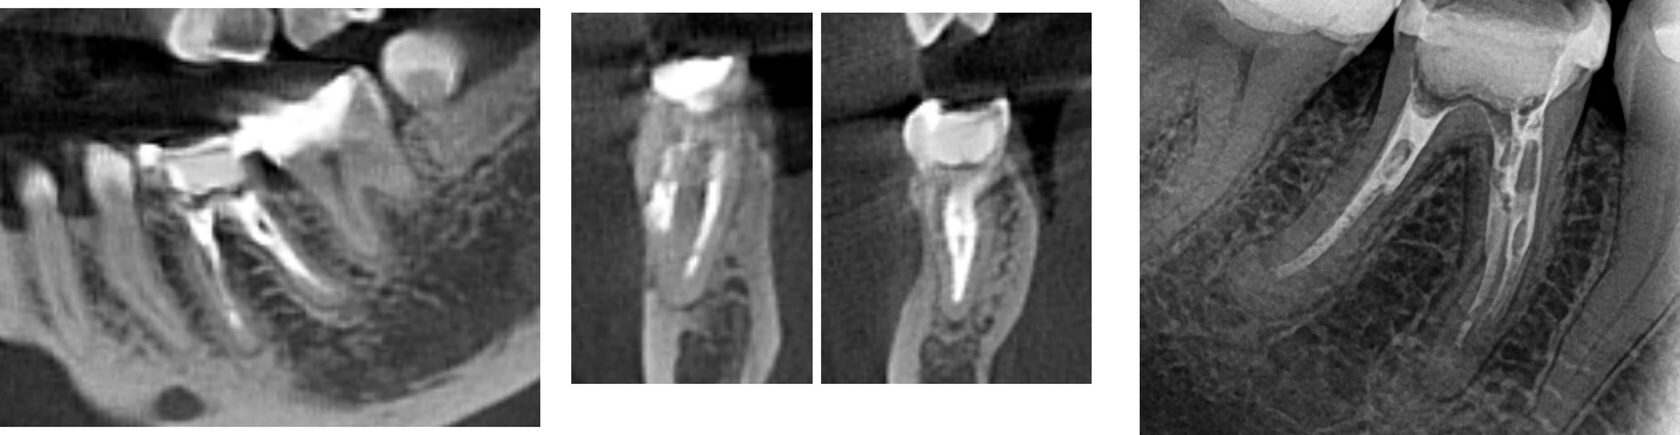

3. Пациентка нарушила график приемов, повторное обращение в клинику через 10 месяцев после начала лечения: временная пломба сохранена, временный обтурационный материал сохранен в корневых каналах, по КЛКТ отмечается значимое уменьшение очага перирадикулярной деструкции. (Фото 5,6,7)